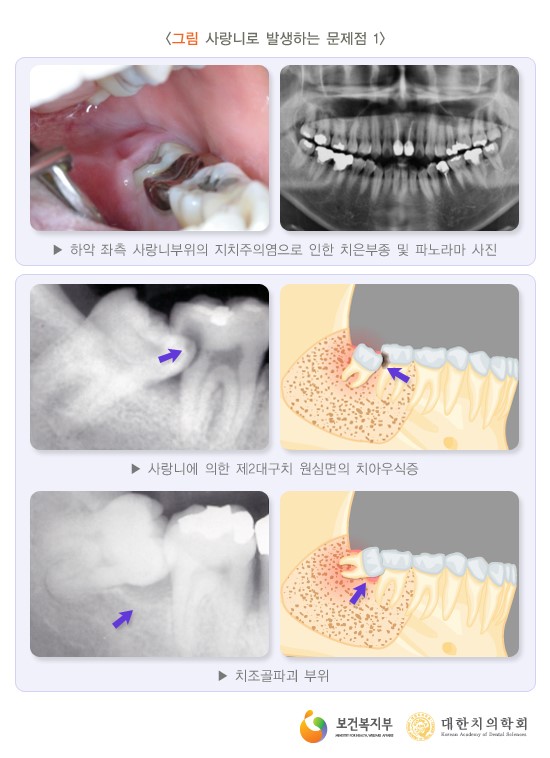

빨간색 원 안 누워있는 사랑니가 보이시죠?

보통 많은 경우에서 사랑니가 옆으로 누워서

나거나 잇몸에 살짝 덮여있어 일부만 보이는

경우, 치아와 잇몸 사이에 세균이 서식해

염증을 일으킬 가능성이 많아 뽑는 것이 좋습니다.

또한 매복 사랑니로 인해 함치성 낭종이 발생될 수

있는데요, 물주머니나 물혹이라 불리는 이 질환으로

주변 뼈가 파괴되면 주변 어금니들에게까지

문제가 생기는 경우가 있어 신속한 치료가 중요합니다